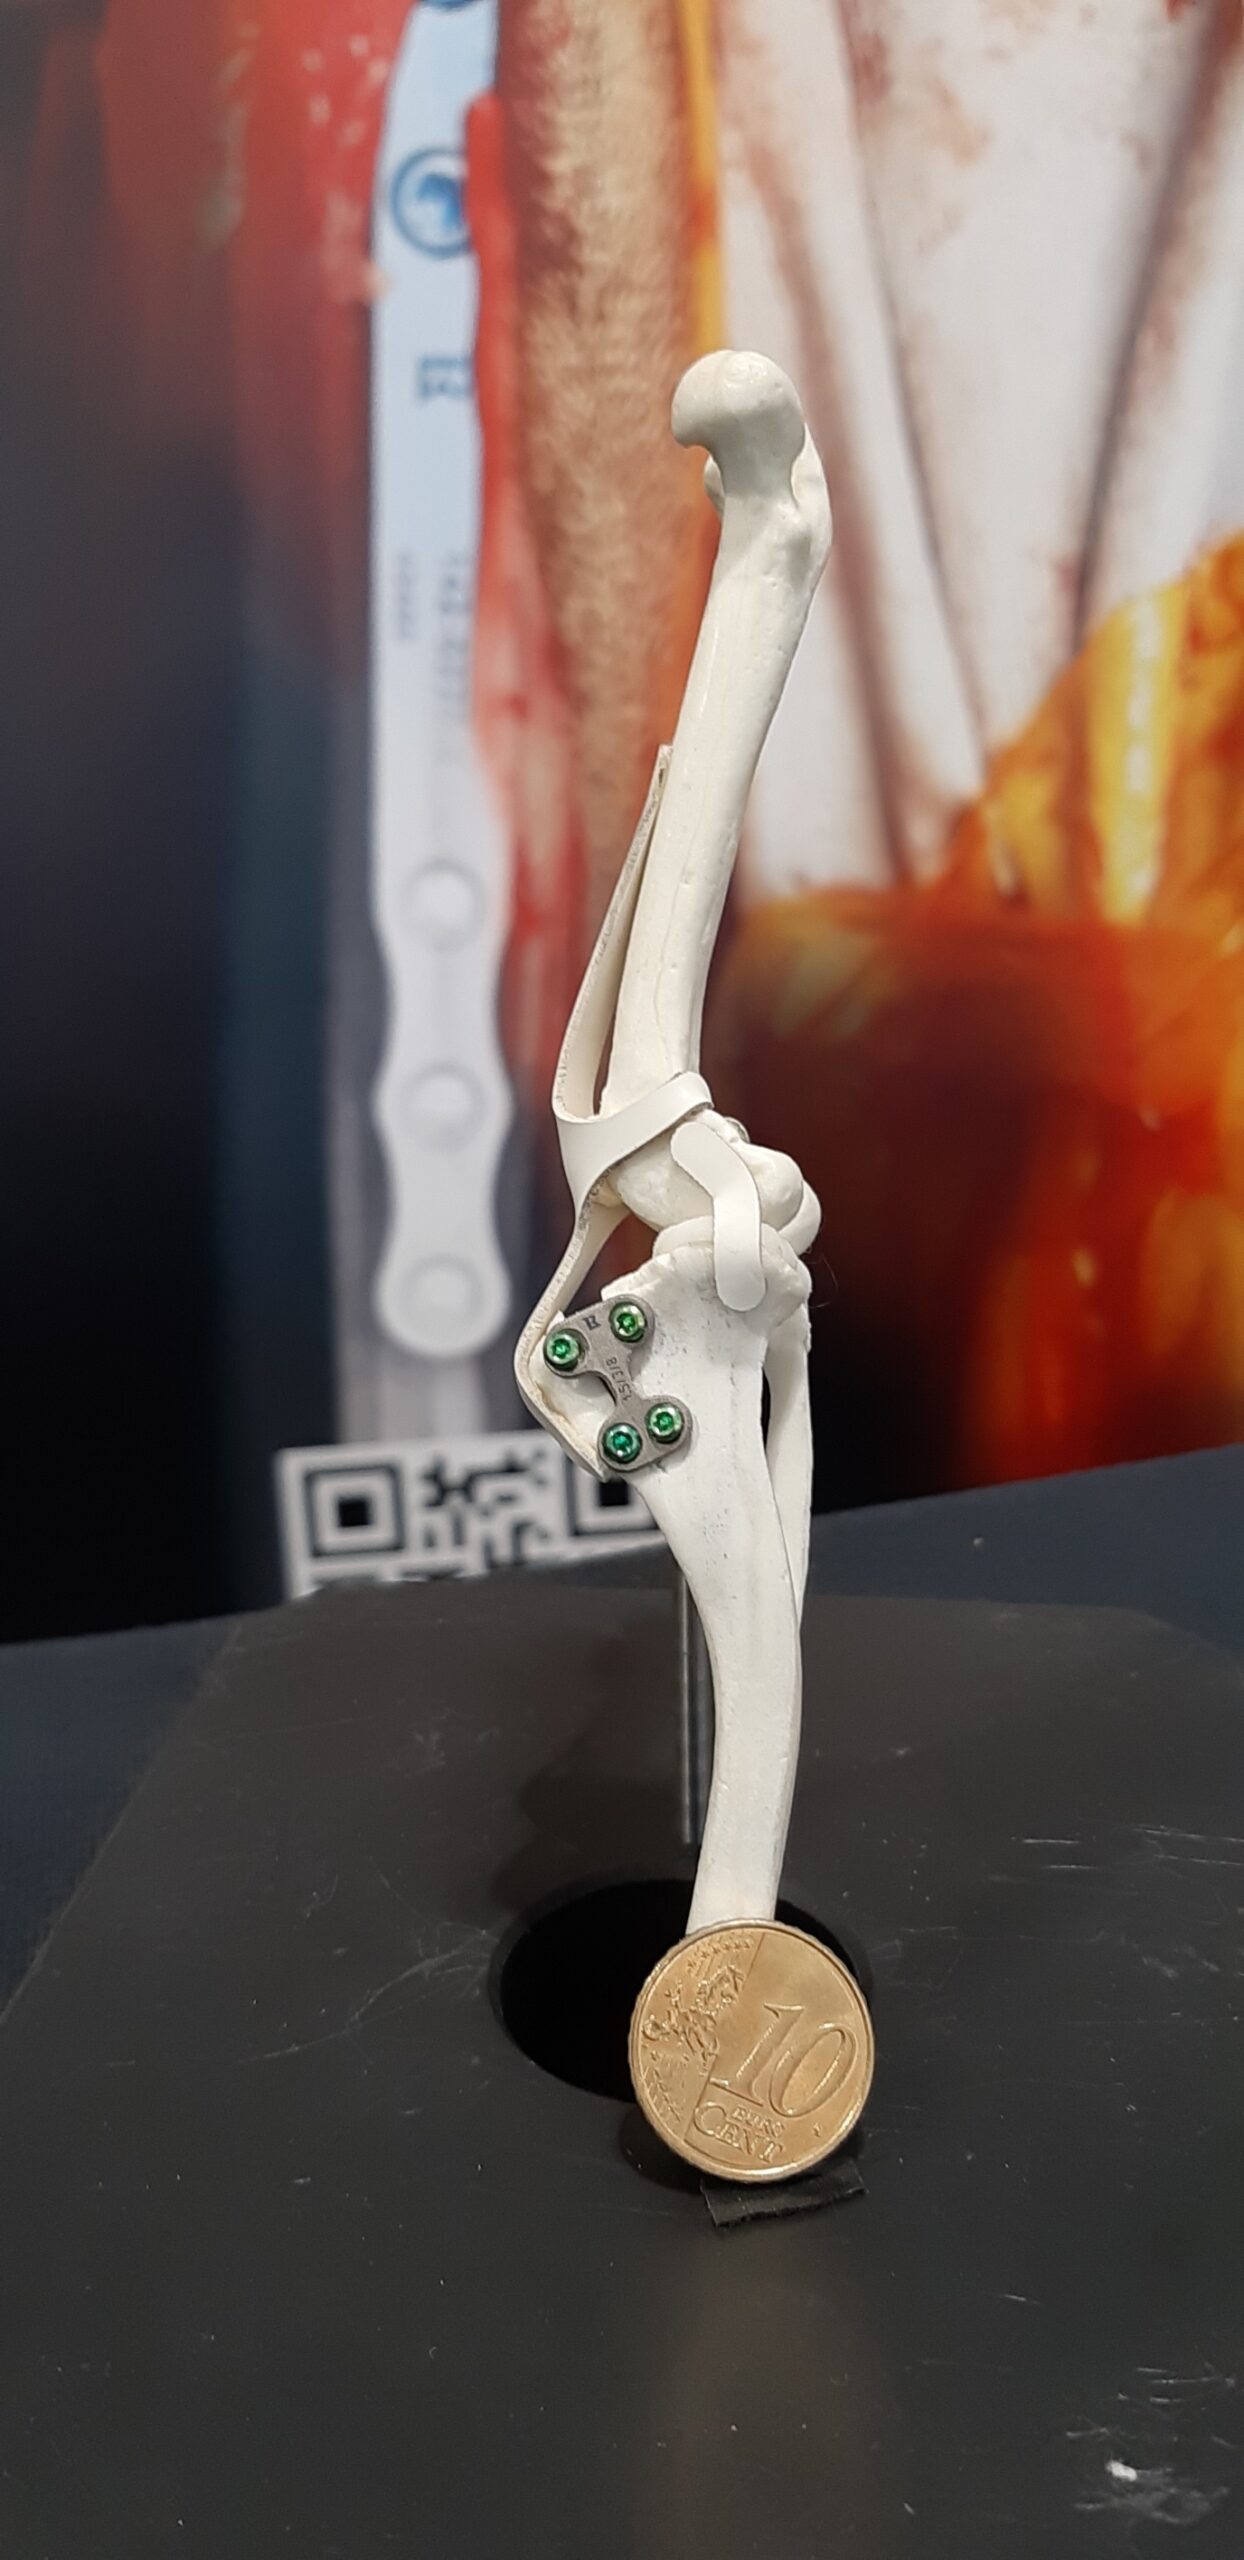

Fracture Treatment in Small Breeds:

Experience of 100 Cases

Tiny TTA RAPID®

Learn how to fix CCL Ruptures in Tiny Animals with the Tiny TTA RAPID® System

Dr. Hugo Schmökel shares with you all his knowledge about CCL Ruptures in Tiny Animals. It will be divided into a theoretical and a practical part. You may ask questions in the comments section of each chapter. Dr. Schmökel will then receive an email with your question.

The only difference between this online course and a wet-lab is the practical part. This course offers a long and detailed "real" surgery with the live comments from Dr. Hugo Schmökel. But you are required to practice on your own with cadavers.

Rapid Luxation

Learn how to fix Patella Luxation with the RAPID LUXATION System

Patella Luxations can be challenging, especially using previous techniques. Luckily, we have developed a seamless, simple technique for addressing both patella luxations and cruciate ligament ruptures.

Dr. Hugo Schmökel shares with you all his knowledge about Patellar Luxations. The course is divided into a theoretical and a practical part. Any questions may be asked in the comments section of each chapter, which will then be received and responded to by Dr. Schmökel.